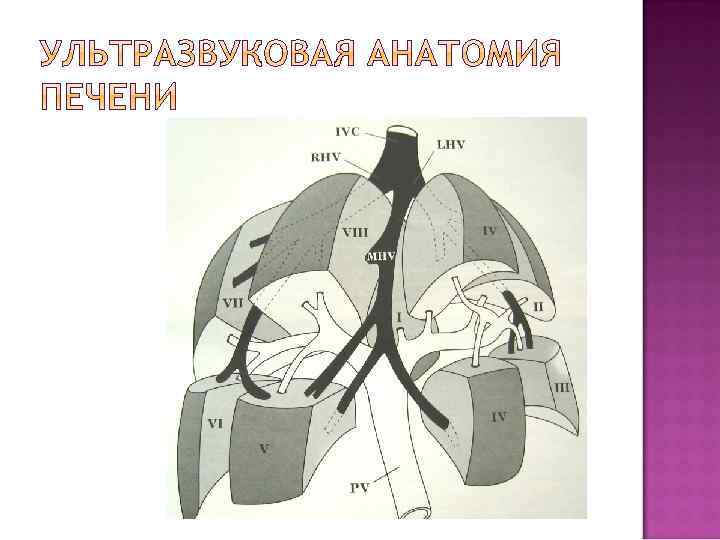

Первый сегмент соответствует хвостатой доле; отделен от 2 и 3 венозной связкой, от 4 воротами печени, от 8 - частично НПВ и устьем правой печеной вены

Второй и Третий соответствуют левой доле; отграничения от других сегментов долевые; второй занимает нижне каудальную часть изображения левой доли с центральным положением сегментарной вены леводолевой ветви воротной вены, а третий – верхне краниальную с центральным положением сегментарной вены леводолевой ветви воротной вены

Четвертый сегмент соответствует квадратной доле; от 3 сегмента – круглая связка и ее борозда, от 1 – ворота печени; четко видимые ориентиры от сегментов правой доли отсутствуют – ложе желчного пузыря граница с 5, а средняя печеночная вена с 8 сегментом

Пятый, шестой, седьмой и восьмой сегменты правой доли – четкие ориентиры между ними отсутствуют Пятый – за ложем желчного пузыря латерально Шестой – латеральнее до края печени (13 часть правой доли) Седьмой – ниже шестого Восьмой (язычковый) – оставшуюся часть правой доли